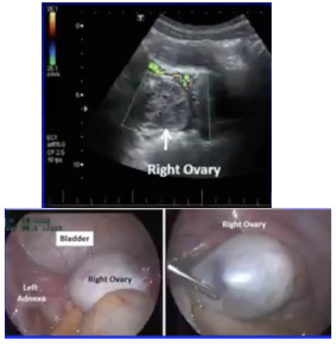

• A 14-year-old girl presents with 2 days of worsening RLQ pain & vomiting.

• US shows normal appendix & enlarged right ovary, with possible torsion.

• At laparoscopy, no torsion is found but an enlarged ovary with no obvious mass is identified.